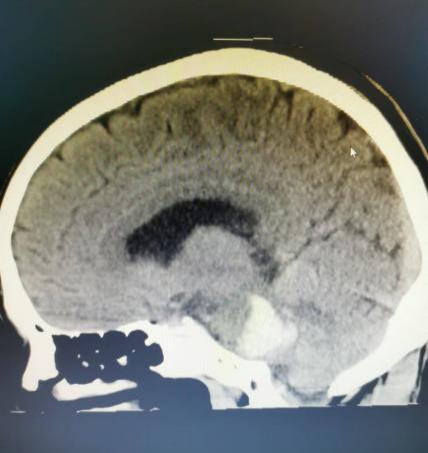

7月下旬的一天,正在开会的李老师突然意识不清伴恶心、呕吐不适,四肢僵直、小便失禁,于是呼叫“120”由我院急诊人员接回,行颅脑CT后提示脑干出血(脑桥出血伴脑内血肿)。

神经外科主治医师唐清明阅片后,诊断患者脑干血肿及呼吸衰竭明确,随时可能呼吸、心跳停止死亡,目前仅脑干血肿清除手术可能有机会挽救患者生命。

脑干出血既往属于神经外科手术禁区,但近年来随着神经外科设备的更新以及技术的飞速发展,我院神经外科团队不懈努力,目前已经熟练掌握此项手术技术。全院各科室争分夺秒,在李老师入院40分钟内其送入手术室,征得家属同意后,唐清明在显微镜下精细手术操作,历经2小时30分钟成功完成手术,术后复查CT提示脑干区血肿清除。术后1周患者恢复自主意识,目前正在康复过程中。